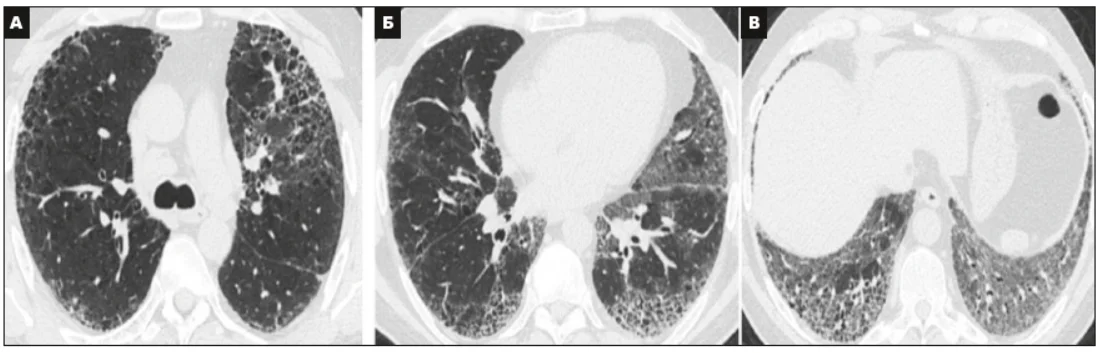

Виділено 4 діагностичні категорії, які складаються з КТ-симптомів (табл. 2 доповнена у 2022 р.). Ці категорії охоплюють ЗІП-патерн (рис. 1), імовірний ЗІП-патерн (рис. 2), невизначений (сумнівний) ЗІП-патерн (рис. 3) і альтернативний діагноз (рис. 4).

Рис. 3. КТВРЗ-патерн невизначеної (сумнівної) ЗІП (А, Б, В).

Поперечні зрізи показують значну інфільтрацію легень, що поєднує в собі стільники, ПМС від легкого до помірного ступеня, асиметричний розподіл між обома легенями і відсутність субплеврального переважання [3].